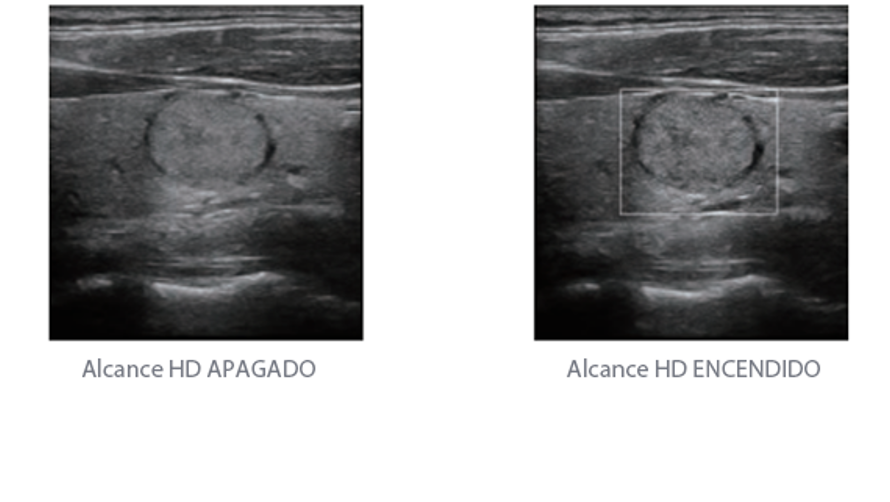

Desde que se fundó la compa?ía, Mindray ha explorado incansablemente nuevas formas de mejorar la confiabilidad del diagnóstico. Con la revolucionaria tecnología de ZONE Sonography?, la nueva plataforma ZST+ de Resona?7 lleva la calidad de la imagen por ecografía a un nivel superior mediante el procesamiento de datos de canal y la adquisición de zona.